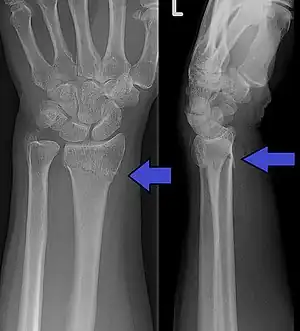

Diagnosis can be made upon interpretation of anteroposterior and lateral views alone.[6]

The classic Colles fracture has the following characteristics:[7]

- Transverse fracture of the radius

- 2.5 cm (0.98 inches) proximal to the radio-carpal joint

- dorsal displacement and dorsal angulation, together with radial tilt[8]

- Radial shortening

- Loss of ulnar inclination≤

- Radial angulation of the wrist

- Comminution at the fracture site

- Associated fracture of the ulnar styloid process in more than 60% of cases.

Bilateral Colles fractures/frontal

Bilateral Colles fractures/lateral

Colles fracture